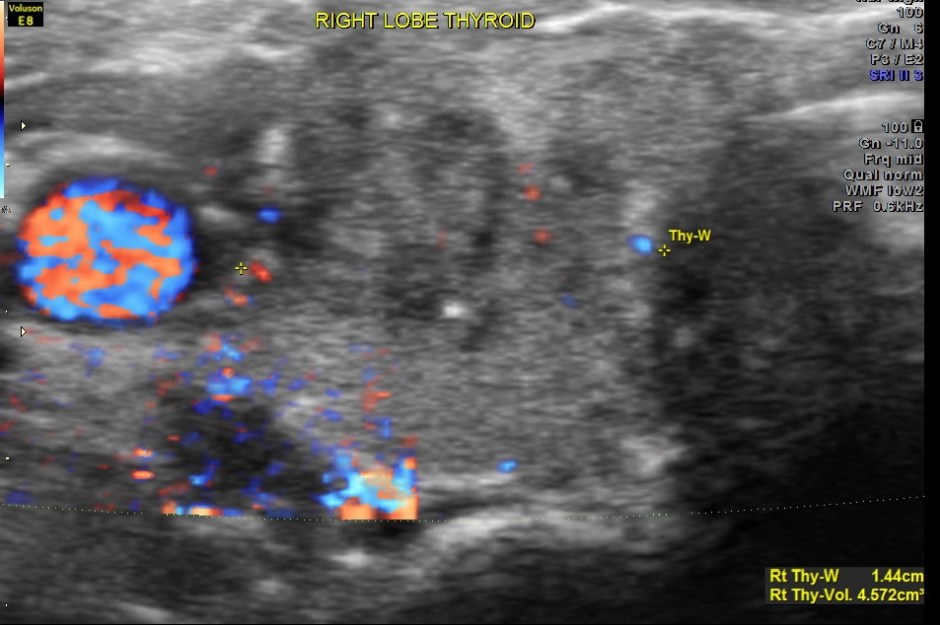

This was a 40 year old lady evaluated for a palpable neck mass on the right side.

Ultrasound revealed he following .

The right lobe of the thyroid revealed an irregular mass , with indistinct margins , punctate calcification and vascularity within and around the nodule.